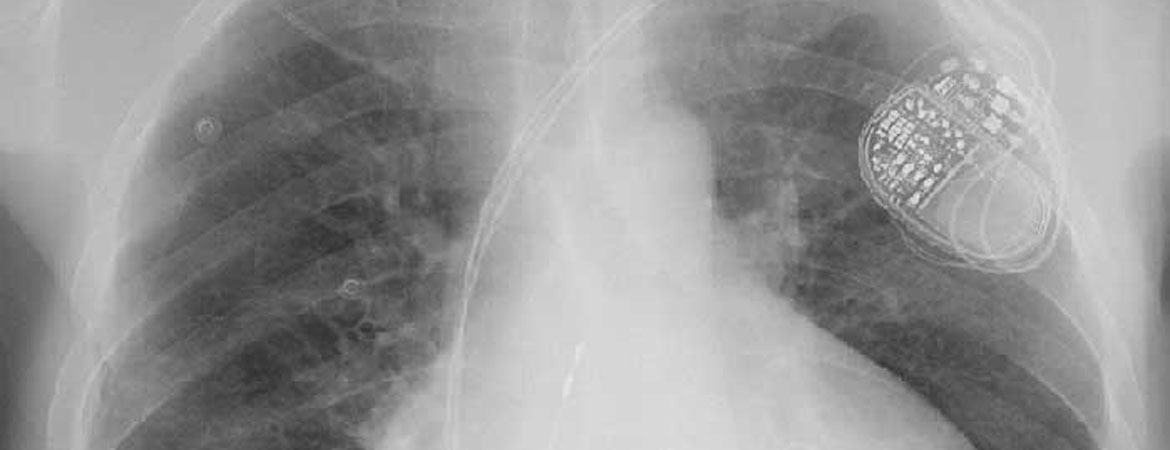

Ivan Zeljkovic, Haran Burri, Alexander Breitenstein, Peter Ammann, Andreas Mueller, Angelo Auricchio, Etienne Delacrétaz, Kenneth Dickstein, Cecilia Linde, Camilla Normand, Christian Sticherling (Author) Cardiac Resynchronisation Therapy (CRT) Survey II: CRT implantation in Europe and in Switzerland Fulltext PDF Fulltext HTML